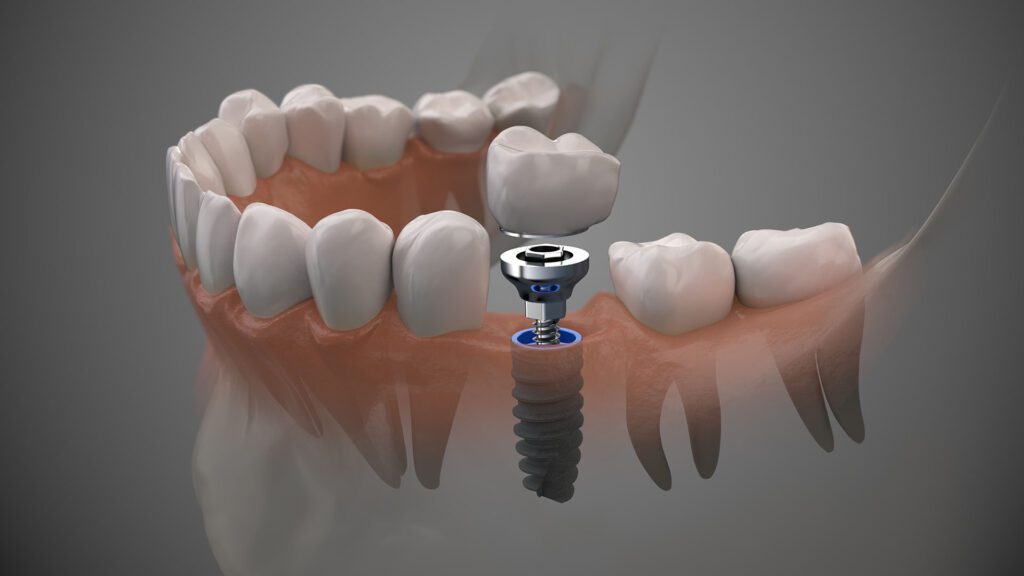

Dental Implants

Dental implants offer a lasting and natural-looking solution for missing teeth, improving oral function, aesthetic appearance, and overall dental health.